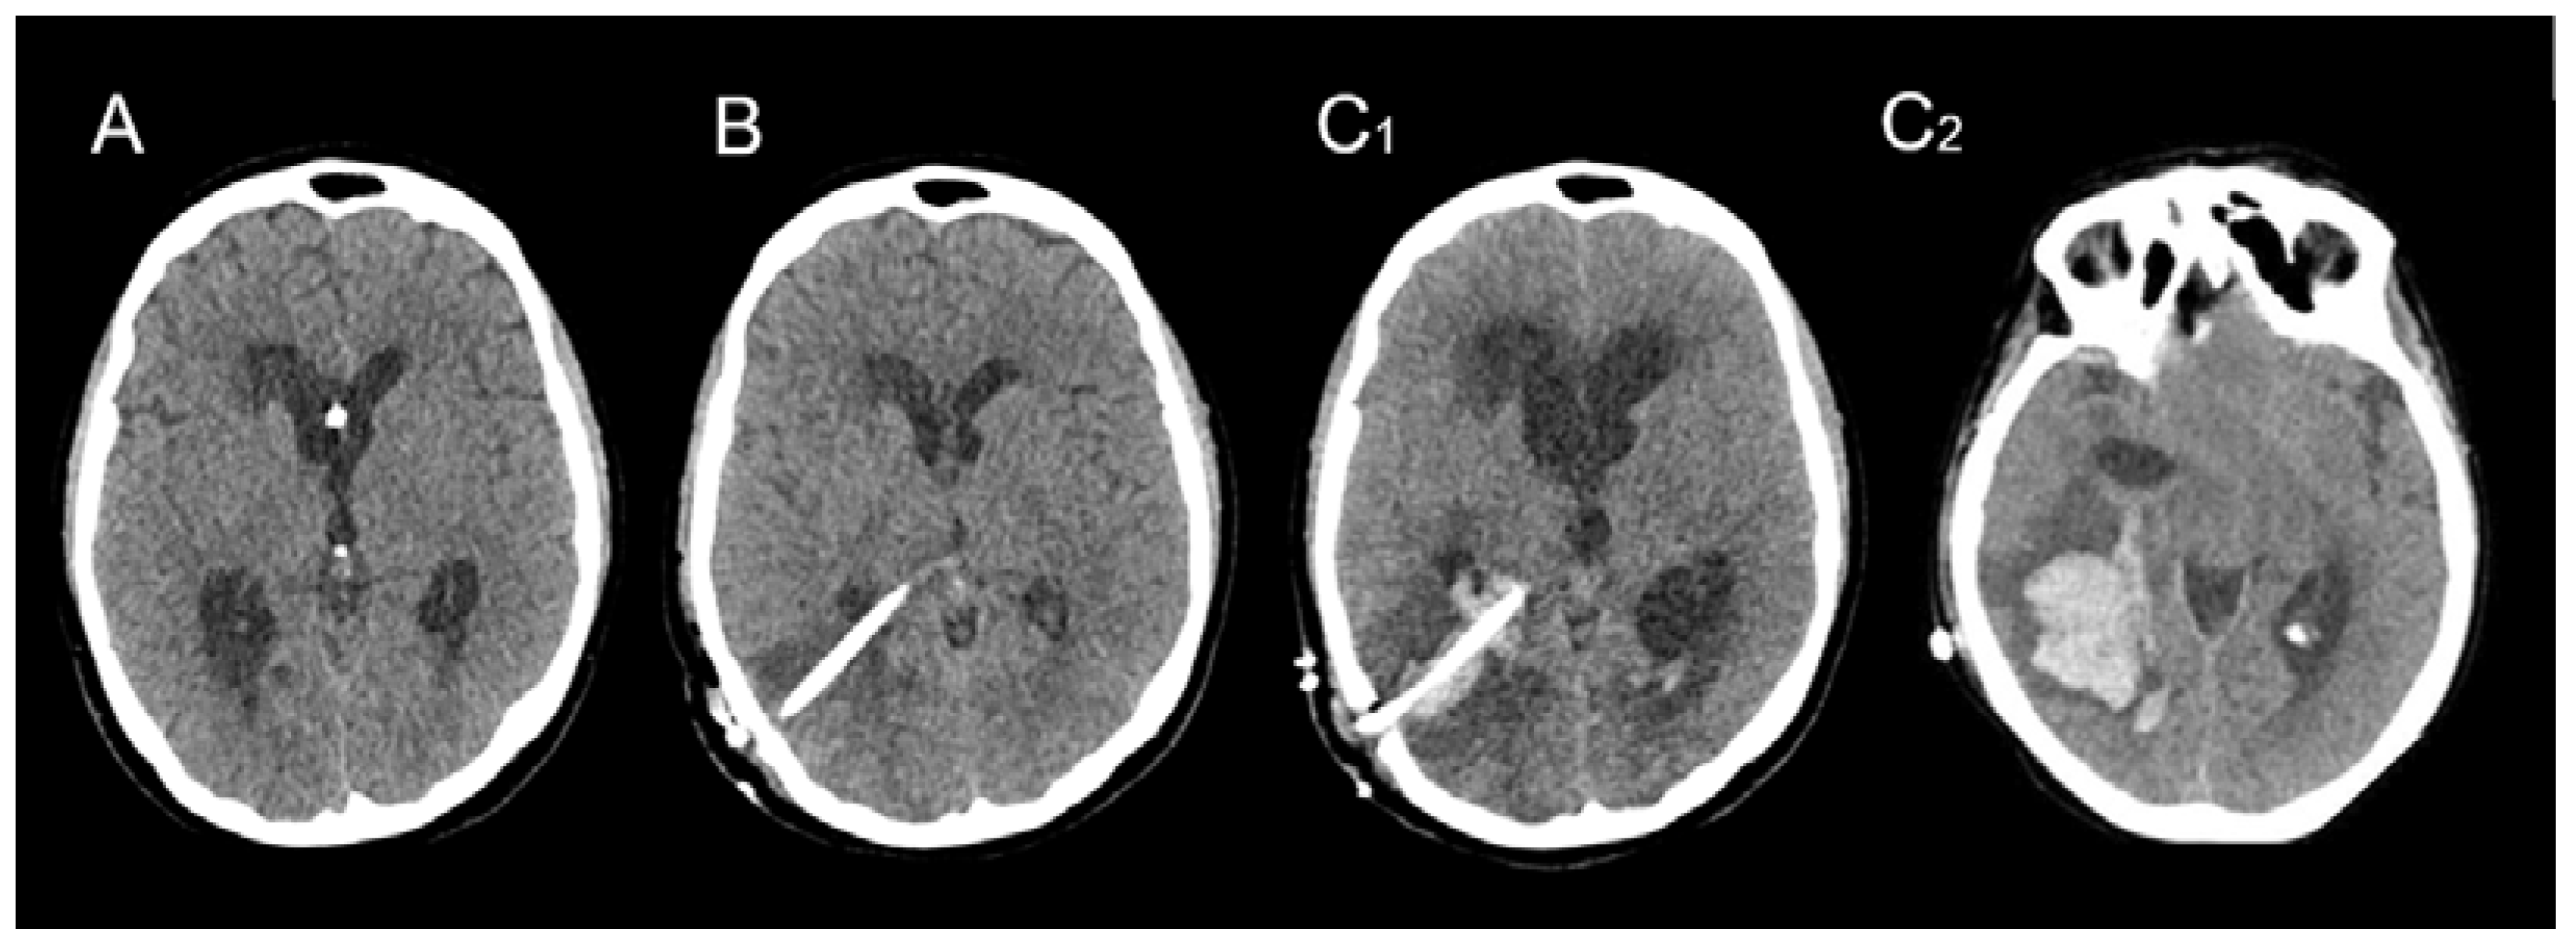

Following the initial hemorrhagic event, all patients underwent a VPS procedure to address chronic hydrocephalus. The median time interval between the initial hemorrhagic event and VPS placement was 25 days, ranging from 19 to 69 days. A preoperative CT scan revealed dilated ventricles without any residual signs of hemorrhage (Figure 4A). None of the patients exhibited apparent risk factors for hemorrhage, and blood clotting tests yielded normal results. Prior to surgery, all patients received low molecular-weight heparin (LMWH) prophylaxis, in accordance to our institutional protocol [,,,] for deep venous thrombosis, which was discontinued one day before the procedure. Standard VPS procedures were performed for all patients, with the ventricular catheter inserted into the right posterior ventricular horn. Adhering to our institutional policy utilizing perioperative imaging-guided system (IGS), successful and uneventful procedures were conducted, requiring only a single attempt for ventricular catheter insertion in all 10 cases. No abnormal bleeding or other perioperative issues were recorded. A Sophysa® ventricular catheter measuring 6 cm in length, with an internal diameter of 1.5 mm and an external diameter of 3.0 mm, was utilized. Following the procedure, all patients recovered consciousness without any complications. Routine post-operative head CT scans were performed within 24 h after surgery, confirming the accurate positioning of the ventricular drain and the absence of hemorrhage (Figure 4B). LMWH prophylaxis was reintroduced following confirmation of a normal post-operative CT scan.

Figure 4.

Illustrative case vignette of one patient’s consecutive CT scans: preoperative scan (A), early post-operative check within 24 h (B) and delayed (5 days) scan after neurological deterioration (C1,C2) showing hematoma at the level of the catheter (C1) and extension below (C2).

Subsequent to the initial procedures, a follow-up CT scan was performed in all patients after a few days, prompted by neurological deterioration. These scans revealed the presence of a substantial intraparenchymal hematoma surrounding the ventricular catheter, distant from the bAVM nidus (Figure 4C1,C2), along with varying degrees of intraventricular hemorrhagic extension.